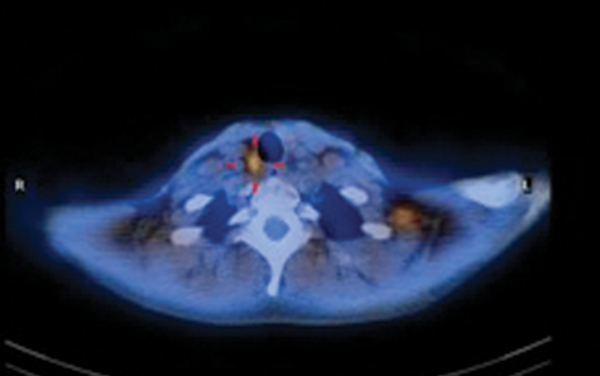

Head and neck cancer and PET-CT

Positron emission tomography-computed tomography (PET-CT) is an imaging technique in which abnormalities of tissue metabolism are precisely superimposed onto the anatomy. It relies on the premise that malignant cells are more metabolically active compared with non-malignant cells. On this basis,...